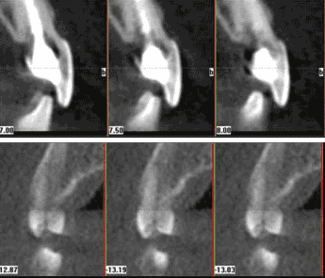

Determining the extent of resorption from conventional radiographs is very difficult. While it is possible to detect external or extra canal invasive resorption, the buccal and lingual areas are very tough, if not impossible to discern. Not so with 3-D, which lets me view the teeth in relation to other anatomical structures sliced in any direction (Fig. 1).